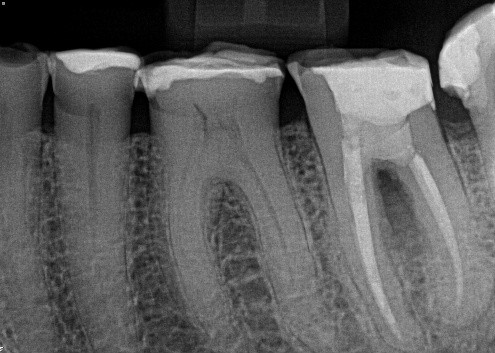

17. (Select ONE or MORE correct answer)

Regarding tooth 4.6, there is evidence of